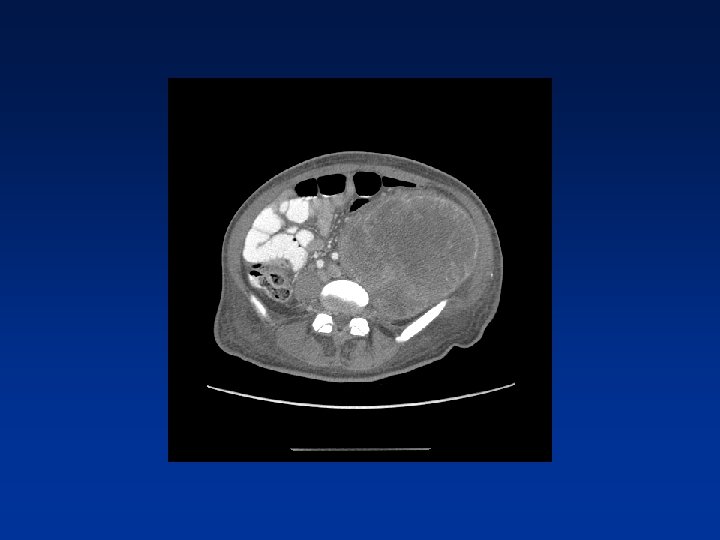

CASE